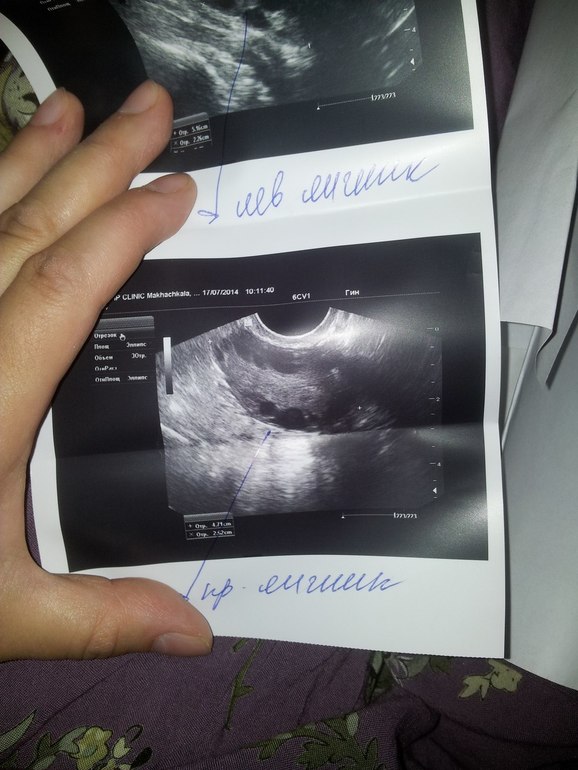

а у меня такой вопрос: на обычном гинек.узи видно уплотненную капсулу на яичниках?

да,она показала,приблизила.там плотная белая капсула вокруг.d31051cddf26ac7708d58ce18d7dc0fd.jpg